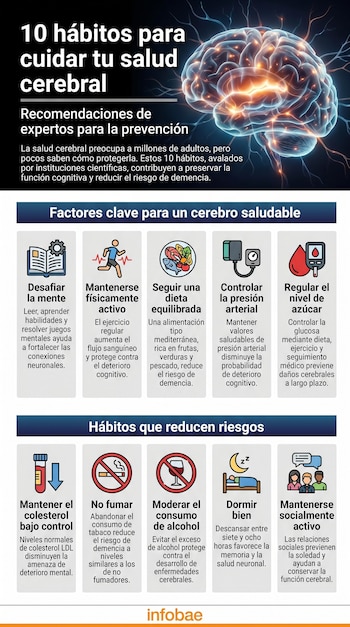

Para la mayoría de los adultos en todo el mundo, la salud cerebral es tan prioritaria como la salud física, aunque existe un notable desconocimiento sobre cómo protegerla eficazmente. Una encuesta realizada por la Asociación de Alzheimer revela que el 99% de los adultos de 40 años o más considera este aspecto tan crucial como el bienestar general, y el 88% la define como “muy importante”. Sin embargo, solo el 9% de los encuestados declara saber realmente mucho sobre cómo cuidar el corazón, según el informe anual publicado por la organización.

Esta percepción se sostiene en parte por la creciente visibilidad pública de enfermedades como el Alzheimer y otras demencias, que afectan a millones de familias en todo el planeta. El interés social en el tema contrasta con las lagunas de información y los desafíos para mantener hábitos saludables a largo plazo.

Como señala Christopher Weber, directivo de la Asociación de Alzheimer, aunque la población comprende de manera general que factores como el sueño, la actividad física, la dieta y la estimulación mental son claves para la salud cerebral, “los datos también muestran lo difícil que puede ser mantener estos hábitos”. La encuesta, realizada en conjunto con la Universidad de Michigan, también refleja que el 82% de los participantes vincula la “buena salud cerebral” con la capacidad de pensar con claridad y tomar buenas decisiones, pero menos de la mitad logra sostener rutinas recomendadas como dormir al menos siete horas o realizar actividad física regularmente.

Cuáles son los principales factores de riesgo

El papel de la genética en la aparición de enfermedades neurodegenerativas como el Alzheimer ha sido ampliamente estudiado. Según información de la Alzheimer Association, determinados genes elevan el riesgo de desarrollar Alzheimer, aunque la presencia de estos factores hereditarios no implica un destino inalterable. Desde la perspectiva de la Mayo Clinic, la herencia familiar puede aumentar la susceptibilidad, pero el deterioro cognitivo resulta, en la mayoría de los casos, de la combinación entre predisposición genética y condiciones ambientales o estilos de vida.

Diversos factores de riesgo modificables han sido identificados por instituciones como Harvard Medical School y la Mayo Clinic. Entre ellos figuran la hipertensión arterial, la diabetes, el colesterol elevado y el tabaquismo, todos asociados a un mayor riesgo de demencia. La casa de estudios estadounidense señala que la presión arterial alta en la mediana edad incrementa la probabilidad de deterioro cognitivo en la vejez, mientras que la diabetes y el colesterol LDL elevado también representan amenazas concretas para la función cerebral. La clínica agrega que la salud de los vasos sanguíneos es determinante, ya que problemas cardiovasculares repercuten directamente en el cerebro.

El enfoque actual de los especialistas se centra en la posibilidad de modificar muchos de esos riesgos a través de intervenciones preventivas. La evidencia sugiere que, aunque la genética establece una base, el entorno y los hábitos cotidianos influyen decisivamente en el desarrollo de enfermedades cognitivas. Por esta razón, tanto la prevención como la detección temprana de factores de riesgo resultan esenciales para preservar la salud cerebral a largo plazo.

Hábitos para mejorar la salud cerebral

1. Desafiar la mente

Realizar actividades que estimulan el pensamiento, como leer, aprender nuevas habilidades, resolver crucigramas o participar en juegos de estrategia, favorece la formación de nuevas conexiones neuronales y puede ayudar a desarrollar una reserva funcional en el cerebro. Según Harvard Medical School, este tipo de estimulación mental incrementa la plasticidad cerebral y protege contra la pérdida celular futura.

2. Mantenerse físicamente activo

El ejercicio regular contribuye directamente a la salud cerebral al aumentar el flujo sanguíneo y oxigenar el cerebro. La Mayo Clinic recomienda realizar actividad física aeróbica moderada varias veces por semana, ya que se ha comprobado que las personas activas tienen menor riesgo de deterioro cognitivo y presentan mejor rendimiento mental con el paso de los años.

3. Seguir una dieta equilibrada

La alimentación juega un papel clave: tanto la Alzheimer Association como la universidad estadounidense sugieren una dieta mediterránea rica en frutas, verduras, pescado, frutos secos y grasas saludables como el aceite de oliva. Este patrón alimentario se asocia con menor incidencia de demencia y mejor funcionamiento cerebral.

4. Controlar la presión arterial

La hipertensión es un factor de riesgo importante para el deterioro cognitivo. Mantener la presión arterial en valores saludables, mediante ejercicio, dieta baja en sodio y control médico, reduce la probabilidad de sufrir demencia en la vejez, según Harvard Medical School y la Mayo Clinic.

5. Regular el nivel de azúcar en sangre

La diabetes no controlada aumenta el riesgo de demencia. Llevar una dieta adecuada, mantener un peso saludable y hacer ejercicio son estrategias centrales. Si los valores de glucosa permanecen altos, la Mayo Clinic recomienda seguir las indicaciones médicas para evitar daños cerebrales a largo plazo.

6. Mantener el colesterol bajo control

Niveles elevados de colesterol LDL (“malo”) están relacionados con mayor riesgo de deterioro cognitivo. El consejo de Harvard y la clínica es adoptar una dieta equilibrada, evitar el tabaco y realizar ejercicio para mantener el colesterol en niveles normales.

7. No fumar

El consumo de tabaco, en cualquiera de sus formas, se asocia al desarrollo de demencia y otras enfermedades vasculares que afectan negativamente al cerebro. La Alzheimer Association destaca que abandonar el tabaquismo puede reducir el riesgo de deterioro cognitivo a niveles similares a los de quienes nunca han fumado.

8. Moderar el consumo de alcohol

Tanto el centro médico como la casa de estudios subrayan que el abuso de alcohol representa un factor de riesgo relevante para la demencia. Se recomienda evitar el alcohol por completo si existen antecedentes médicos.

9. Dormir bien

Un descanso nocturno adecuado, de al menos siete u ocho horas seguidas, es esencial para la consolidación de la memoria y la eliminación de proteínas anormales en el cerebro. La Mayo Clinic sugiere consultar a un especialista si existen problemas de sueño, como la apnea, para evitar consecuencias negativas a largo plazo.

10. Mantenerse socialmente activo

La interacción social frecuente protege contra la depresión y el estrés, dos factores asociados a la pérdida de memoria. Según la Mayo Clinic y la Alzheimer Association, fortalecer los lazos sociales y participar en actividades grupales ayuda a mantener la función cerebral y reduce el riesgo de aislamiento, un factor de riesgo para la demencia.